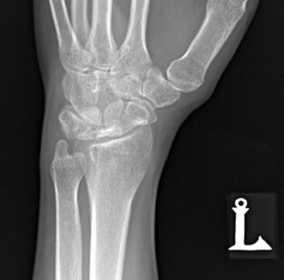

| PA Wrist | ANATOMY: all carpals including midmetacarpals and distal radius/ulna CRITERIA: true PA is marked by symmetry of proximal metacarpals carpals should be free of superimposition of the metacarpals and radius/ulna POSITIONING: CR perpendicular @ midcarpals |

| PA Wrist | wrist externally rotated - joint spaces closed, proximal metacarpals superimposed, carpals superimposed radiocarpal joint is closed |